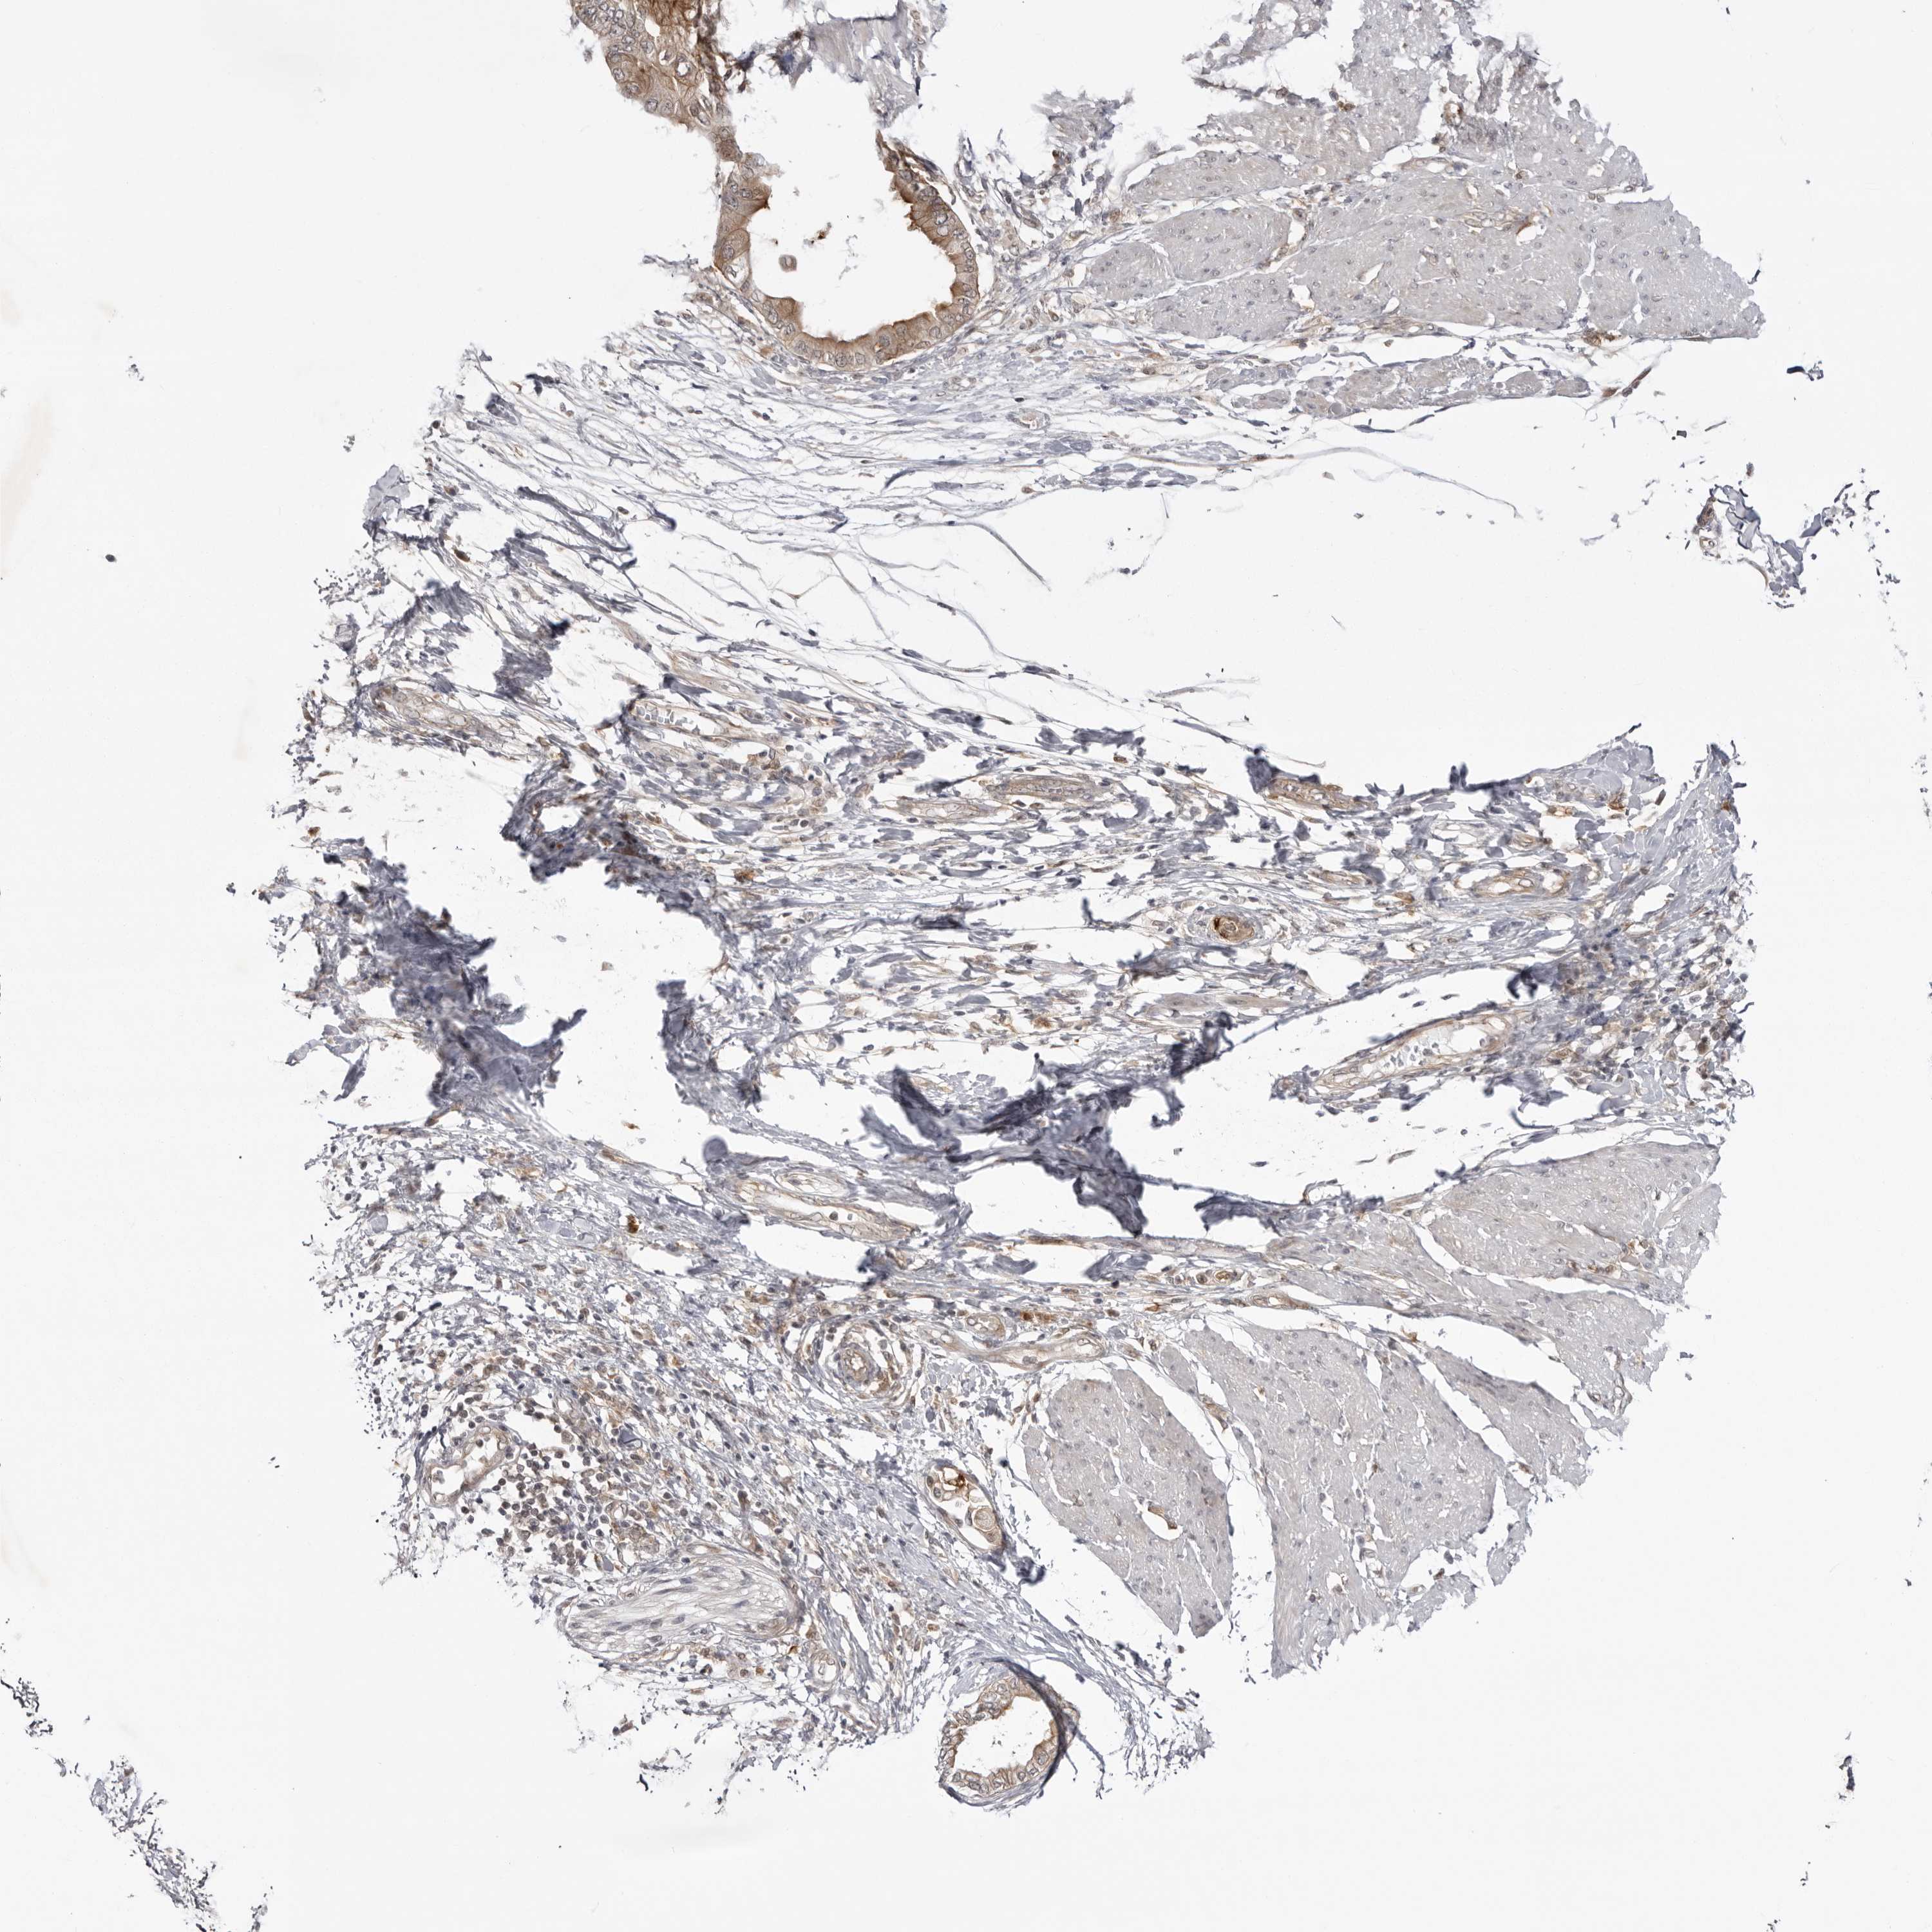

PANCREATIC CANCER - Protein expressioni

A mouse-over function shows sample information and annotation data. Click on an image to view it in a full screen mode. Samples can be filtered based on level of antibody staining by selecting one or several of the following categories: high, medium, low and not detected. The assay and annotation is described here.

Note that samples used for immunohistochemistry by the Human Protein Atlas do not correspond to samples in the TCGA dataset.

Antibody stainingi

Antibody staining in the annotated cell types in the current human tissue is reported as not detected, low, medium, or high, based on conventional immunohistochemistry profiling in selected tissues. This score is based on the combination of the staining intensity and fraction of stained cells.

Each image is clickable and will lead to virtual microscopy that enables deeper exploration of all samples and also displays staining intensity scores, fraction scores and subcellular localization as well as patient and tissue information for each sample.

Antibody HPA023389

Antibody HPA027762

Staining

High

Medium

Low

Not detected

Intensity

Strong

Moderate

Weak

Negative

Quantity

>75%

75%-25%

<25%

None

Location

Nuclear

Cytoplasmic/membranous

Cytoplasmic/membranous,nuclear

Adenocarcinoma, NOS